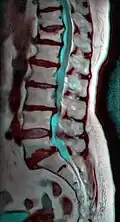

MRI of L5-S1 anterolisthesis -

Magnetic resonance imaging (MRI)

Magnetic resonance imaging is the preferred advanced imaging technique for evaluation of spondylolisthesis.[35] Preference is due to effectiveness, lack of radiation exposure, and ability to evaluate for soft tissue abnormalities and spinal canal involvement.[35][36] MRI is limited in its ability to evaluate fractures in great detail, compared to other advanced imaging modalities.[37]